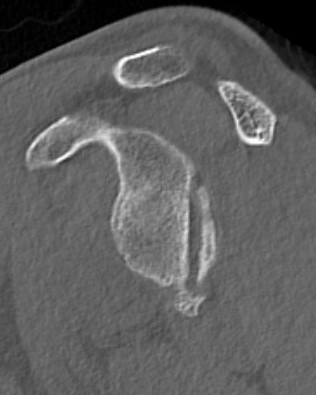

CT scan

Confirms dislocation

Reverse Hill Sachs

Humeral head defect

- caused by impaction of anterior humeral head on posterior glenoid

- intra-articular

- measured as a percentage of the articular surface

Lesser tuberosity fractures

Posterior glenoid fractures / bony bankart